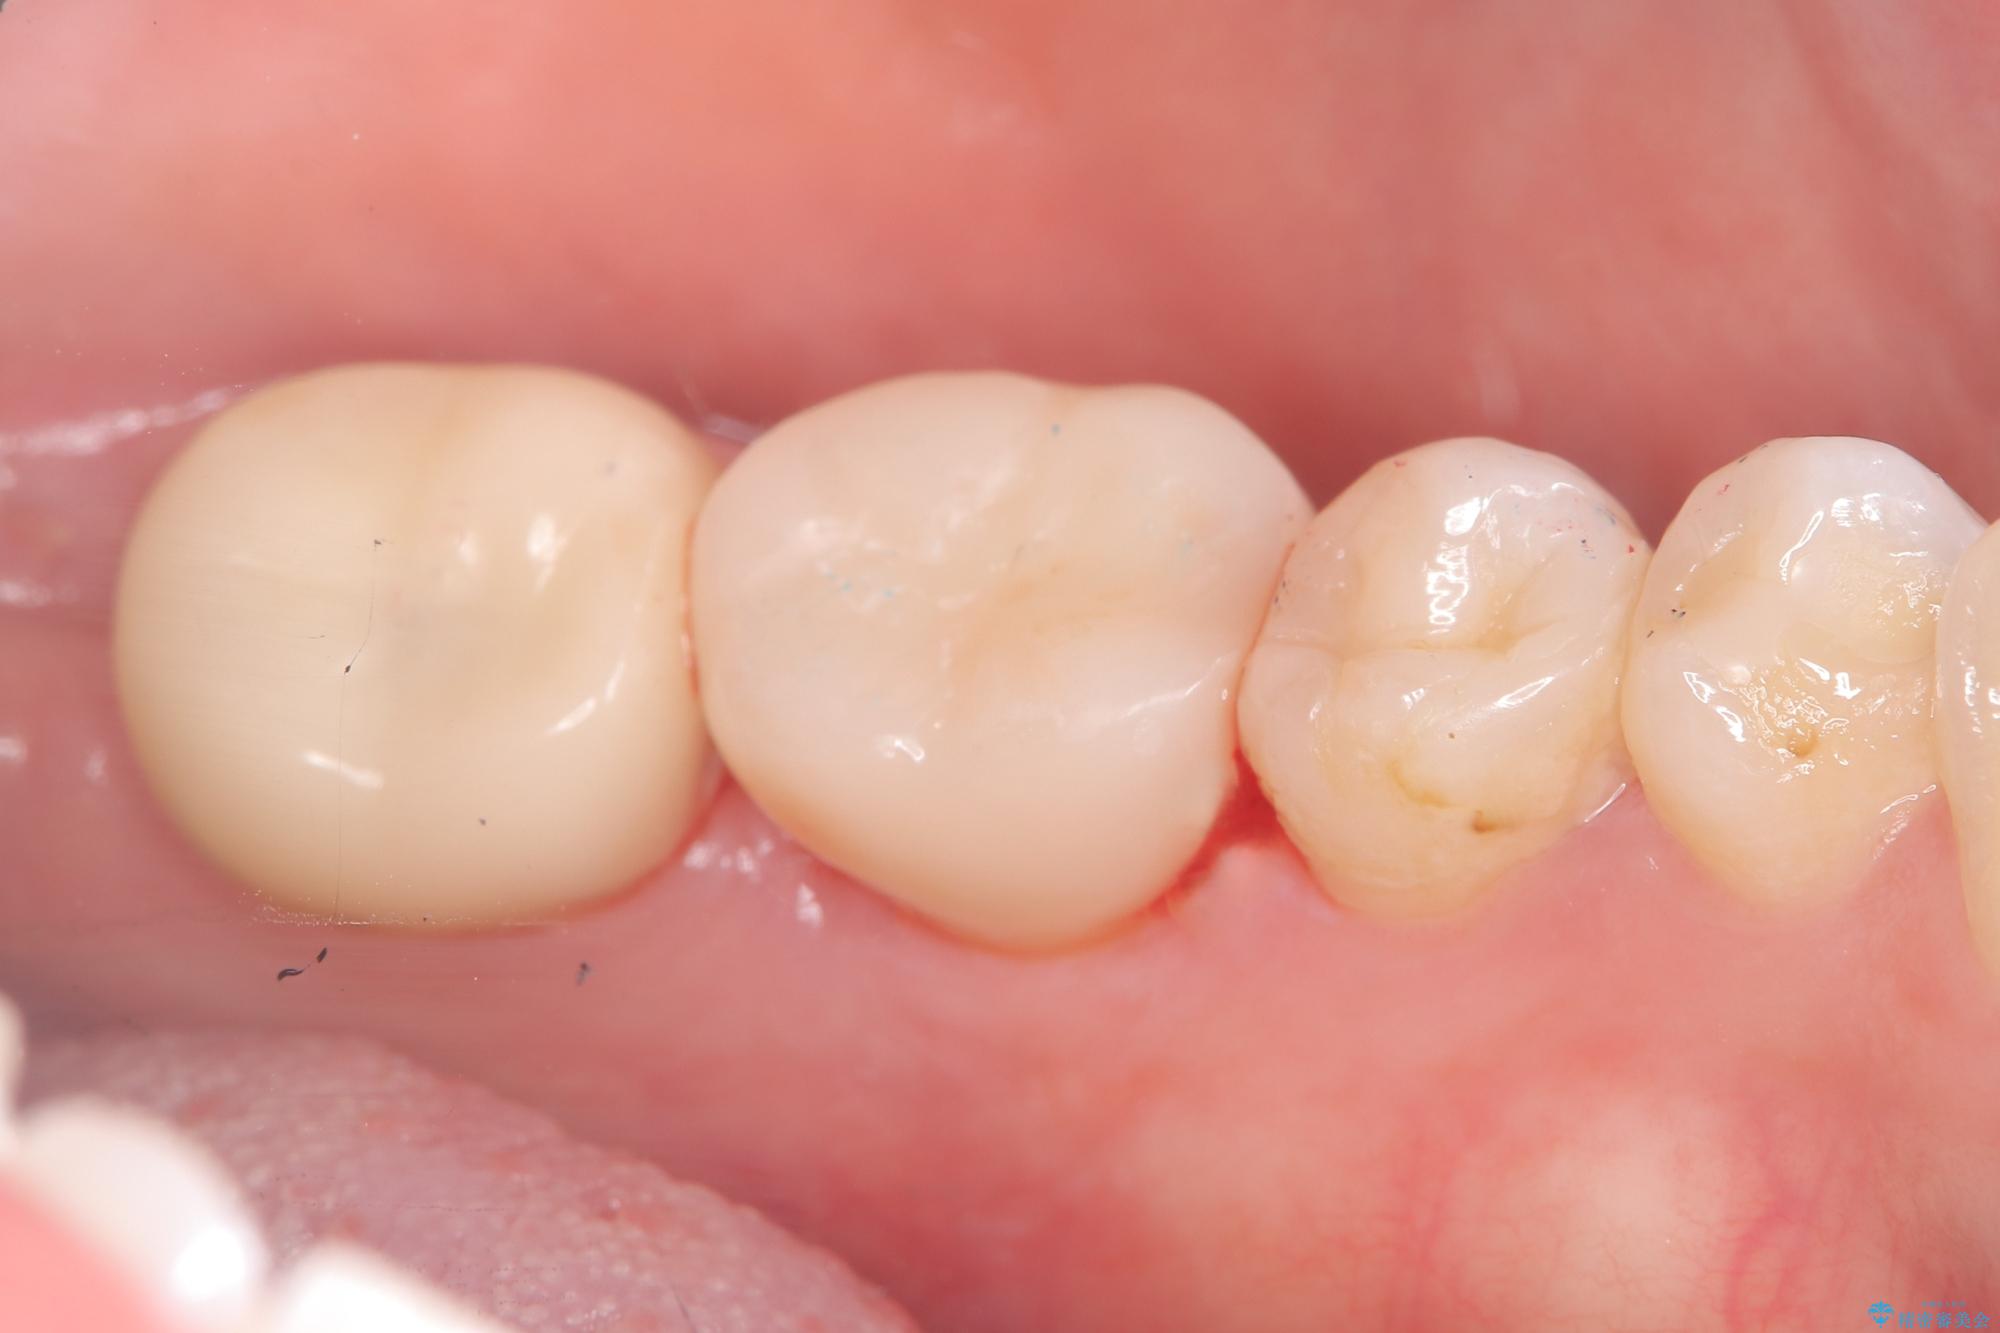

保存が難しい左下6番目の歯を抜歯し、左下8番目の歯(親知らず)を抜歯窩に移植しました。歯牙移植後の動揺防止のため暫間固定を行っています。

骨との定着を確認し、今後矯正治療を行う予定のためレジン冠をセットしています。